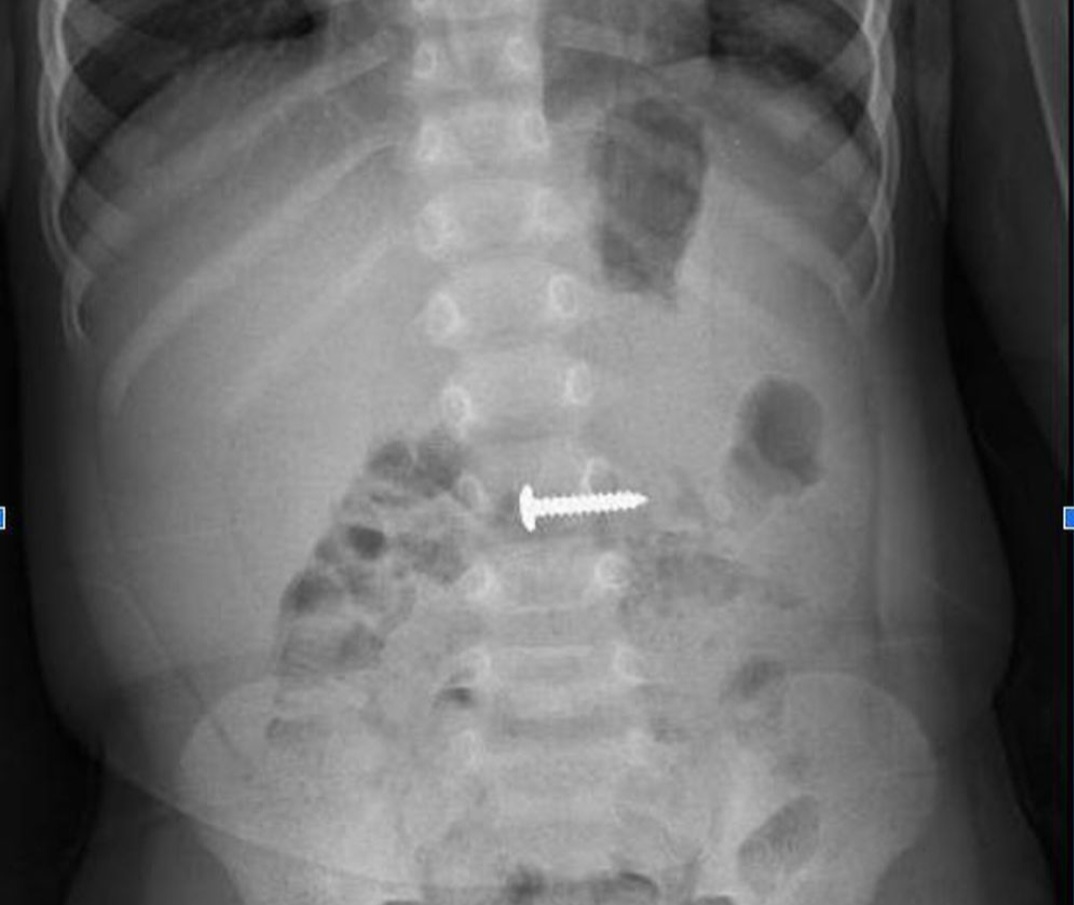

រូបភាពកាំរស្មីអ៊ិចនៃវត្ថុបរទេស

នៅទីនេះ អ្នកជំងឺត្រូវបានពិនិត្យដោយវេជ្ជបណ្ឌិតនៃនាយកដ្ឋានវះកាត់ទូទៅនៃមន្ទីរពេទ្យ Quang Tri General Hospital និងបានបញ្ជាឱ្យថតកាំរស្មីអ៊ិចពោះ ដែលបានរកឃើញវត្ថុបរទេសនៅក្នុងបំពង់រំលាយអាហារដែលមានទំហំ 24.15 មីលីម៉ែត្រ។